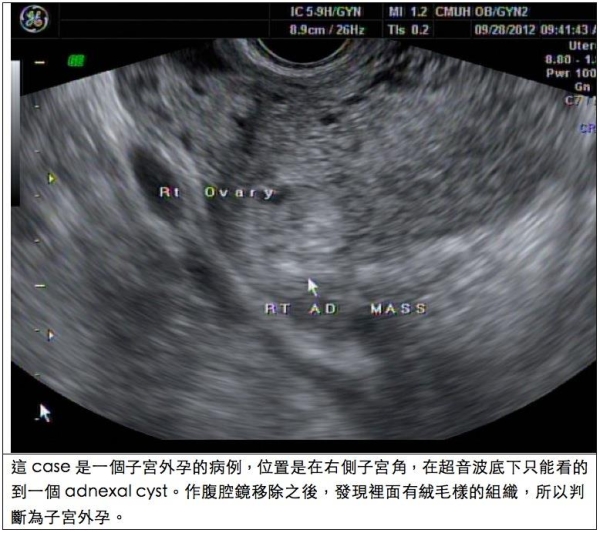

但卻因為第一胎就發生子宮外孕,我切除了左側卵巢和輸卵管。